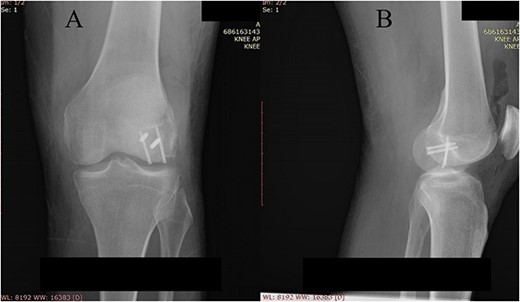

Postoperative plain X-ray of the left knee. (A) Anteroposterior view. (B) Lateral view.

One month after index surgery, the patient was readmitted for the second intervention. In spinal anesthesia, the left knee was positioned for routine arthroscopy. During the procedure, it was concluded that the achievement of proper anatomical fragment repositioning and fixation is unobtainable. Therefore, conversion to arthrotomy followed via the lateral parapatellar approach. Fragments were fixed with two titanium headless compression screws (3.5 mm) (Fig. 4). The second postoperative period was uneventful. Early range of motion exercises started on postoperative Day 2. The patient was discharged on postoperative Day 4. The rehabilitation period lasted 4 weeks. Weight-bearing was allowed at Week 8 after surgery.

Two years following the injury, the patient had a complete and painless range of motion in the left knee (Fig. 5).